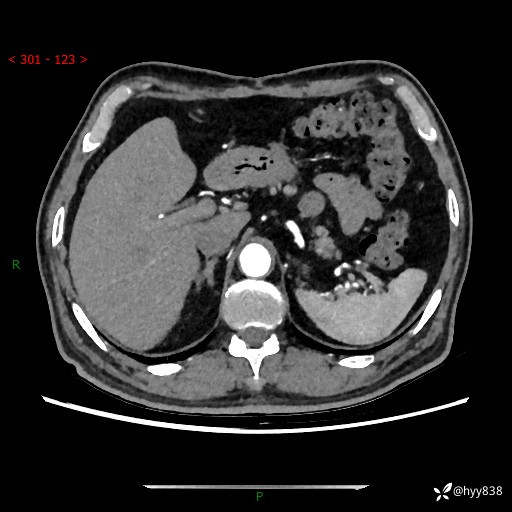

【检查】:胰腺CT平扫+增强